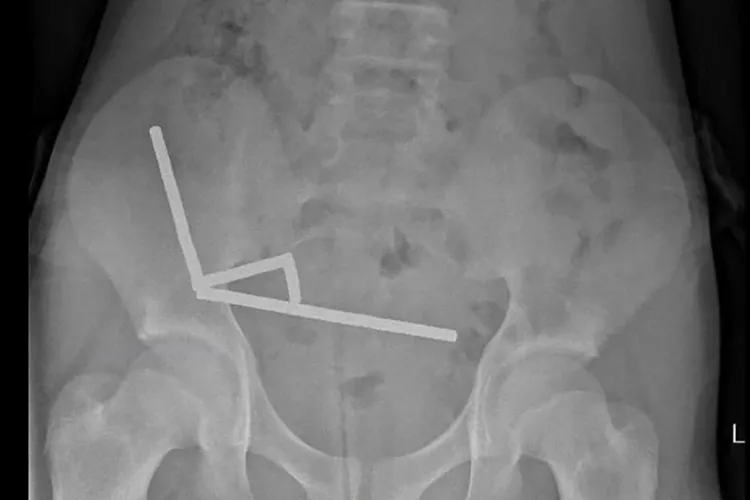

Ia dilaporkan menelan magnet seminggu sebelumnya. Para peneliti mengatakan sinar-X telah diambil dan menunjukkan “empat rantai magnet linier” yang saling terhubung, terdiri dari apa yang ditunjukkan oleh anak laki-laki tersebut sebagai “sekitar 80–100 magnet (neodymium) berdaya tinggi berukuran 5×2 mm” yang diduga dibeli dari pengecer daring Temu.

Foto-foto yang dipublikasikan dalam penelitian tersebut menunjukkan proses pengambilan kembali dan menunjukkan magnet-magnet tersebut berada di bagian-bagian usus yang terpisah tapi melekat satu sama lain karena gaya magnet.